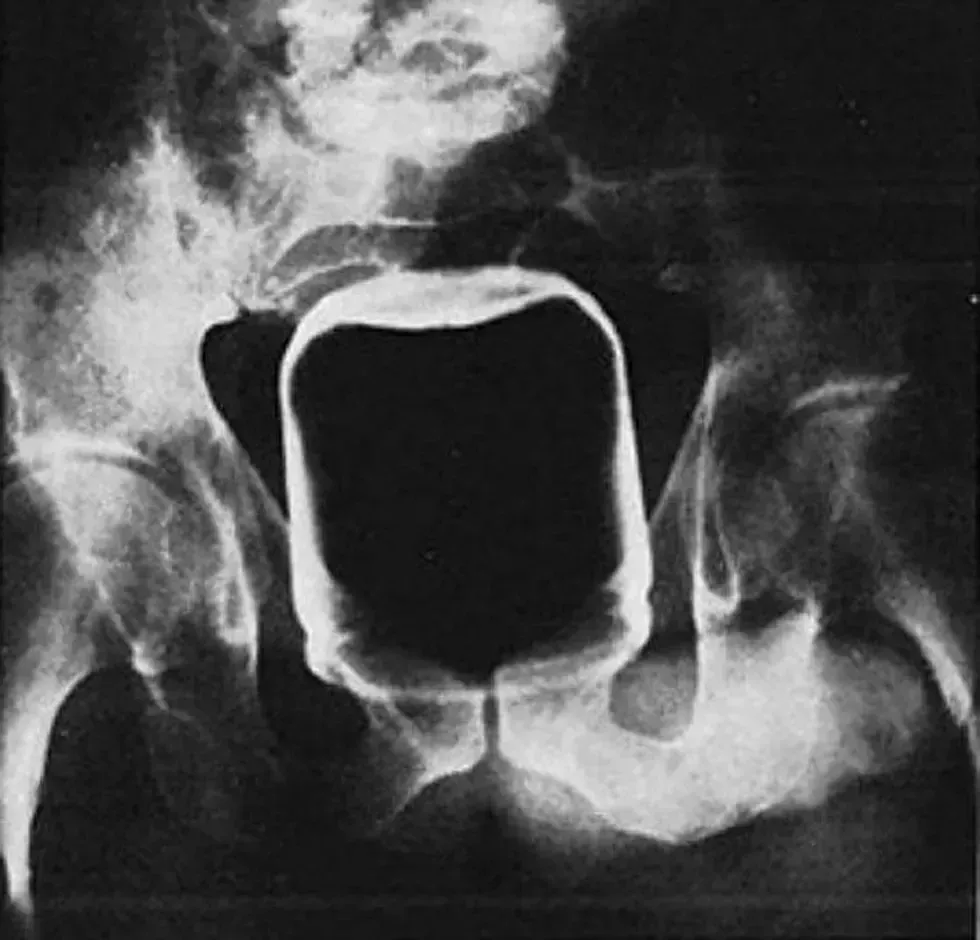

20. A billiard ball